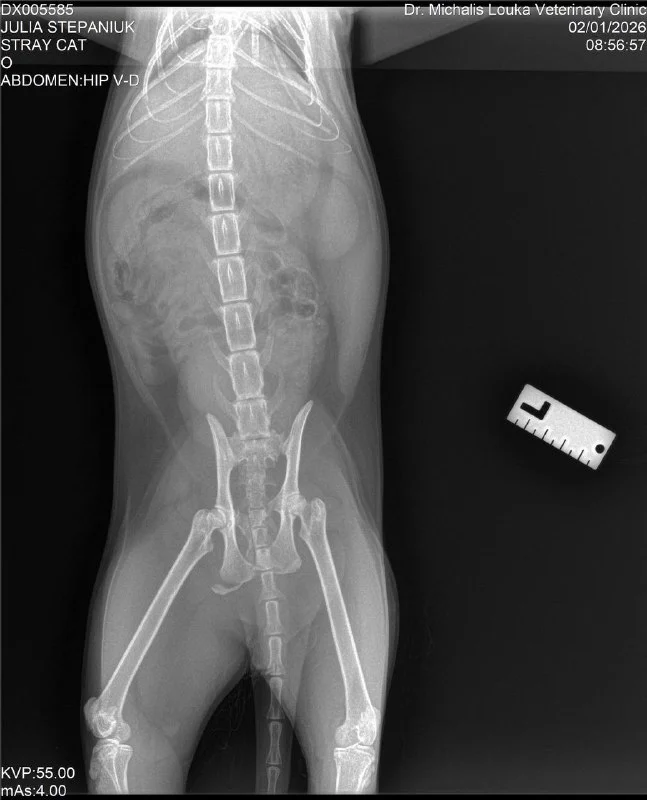

Right now CAR HIT this cat front of me.😧

Итак, новости. Сегодня заехала к котику. Его прооперировали, буквально собирали челюсть. Таз тоже переломан, но там операция не нужна. Сейчас стоит трубка в шее до желудка, чтобы кормить.

Получила предварительный счет на сегодня 😵💫

Умоляю, помогите оплатить 🙏

Revolut: +35799 377 950 (nadzeyjhpd)

К этому же номеру quick pay Bank of Cyprus

PayPal: [email protected]